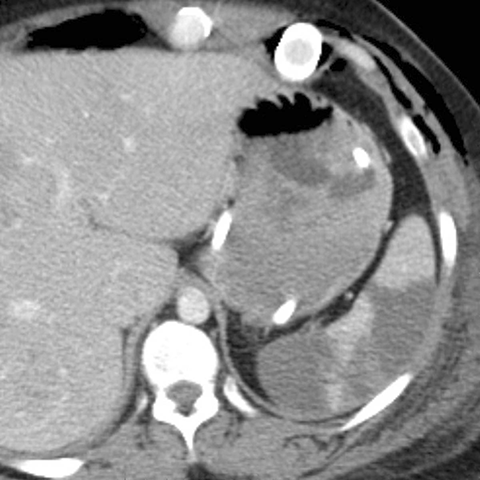

Acute splenic infarction (CT)